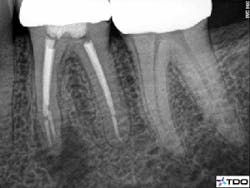

Figure 2 demonstrates a case with failing endodontic therapy. The mesial canals show inadequate obturation, and a periradicular radiolucent area is apparent. The tooth was retreated, and figure 3 shows the one-year follow-up. Note the resolution of the radiolucency. This case demonstrates the concept of removing the etiology of the bacteria with nonsurgical treatment.